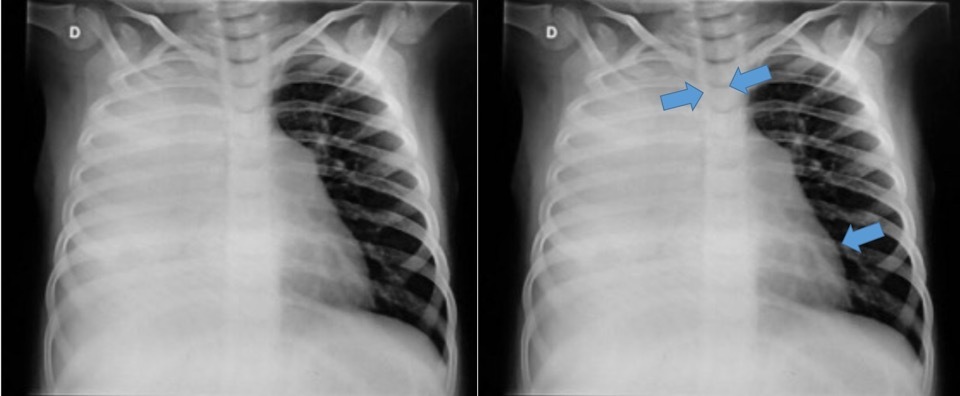

Tórax Opaco - Atelectasia

Tórax Opaco

DP

Laurell